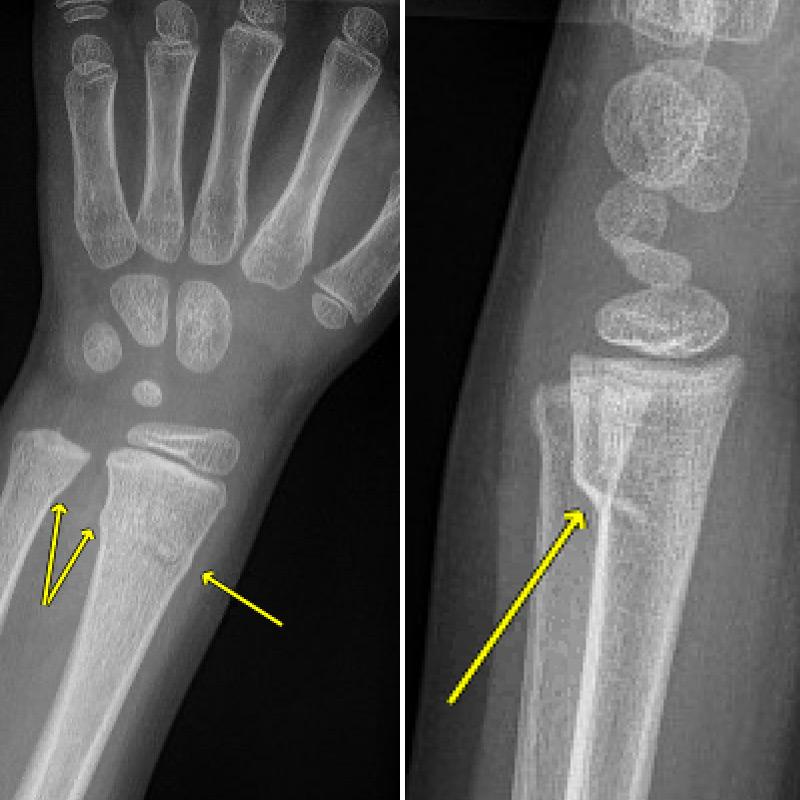

After a physical exam, your child will likely need an X-ray to confirm any buckle or other fractures and show how damaged their bones are.